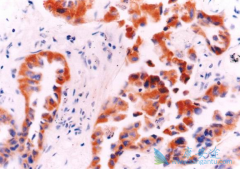

近日,Annals of Thoracic Surgery 上报道了一例肺癌腺癌患者,在经过吉非替尼治疗后转变为 肺癌鳞癌 的病例。吉非替尼是一代EGFR-TKI,对于具有EGFR突变的肺癌腺癌十分有效。那该患者出现这种转变是怎么回事呢?免疫组化分析根据肿瘤细胞对于 TTF-1 以 ...